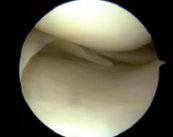

¿Qué es un menisco y su importancia en la rodilla?

No tener un menisco en buen estado como amortiguador puede tener consecuencias significativas para la rodilla.